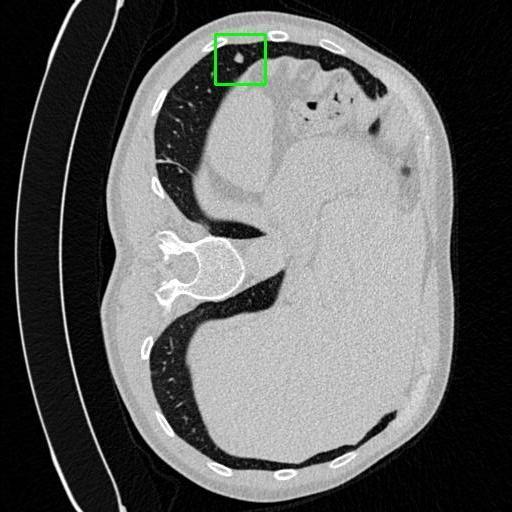

We developed an AI-based system using deep learning models for analyzing lung CT scans to detect and classify pulmonary nodules. We chose the YOLOv11 architecture for its enhanced object detection capability and adapted it specifically for medical imaging, incorporating pixel-level precision and severity classification.

Classification into three severity levels with colored bounding boxes.

Successfully built and deployed an AI model (YOLOv11) capable of detecting lung nodules in CT scans with high accuracy and real-time performance.

Designed a severity classification system that categorizes nodules into null, moderate, and severe using colored bounding boxes, assisting in rapid clinical decision-making.